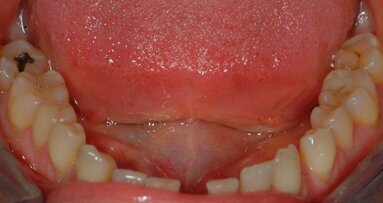

L’irrigazione manuale dinamica: In genere, l’irrigazione manuale dinamica si ottiene con l’ausilio di un cono di guttaperca che viene mosso con movimenti di up/down sulla lunghezza di lavoro con escursioni di 2/3 mm dopo avere ultimato la preparazione (Fig. 11). “Recent studies have shown that this irrigation technique is significantly more effective than an automated-dynamic irrigation system and static irrigation [...]”15-16. Di sicuro questa metodica semplice e poco costosa riesce a mettere in movimento gli irriganti all’interno dei canali spostando questi con una certa efficacia, come dimostrato anche su modelli sperimentali, riuscendo ad agire anche sui canali laterali più coronali17 (Fig. 12).